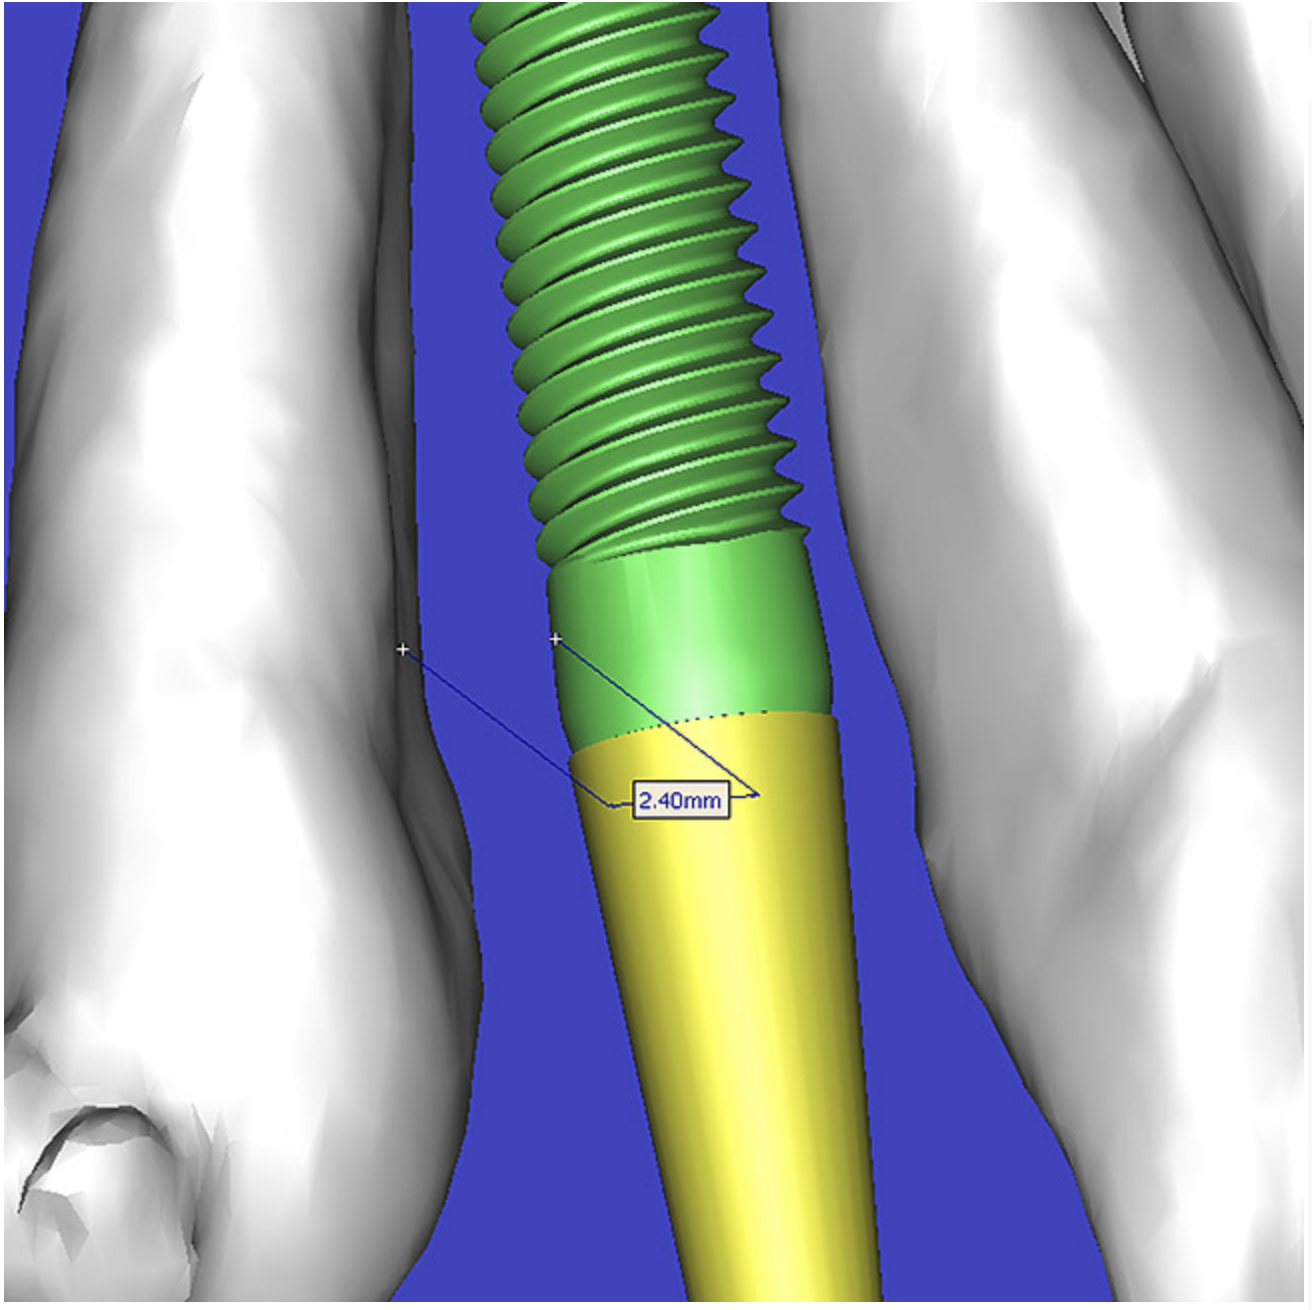

By using interactive treatment-planning software, the author was able to assess implant-to-tooth distances based on actual undistorted measurement of distances at both the crest (Figure 11A) and the apex (Figure 11B) of the implant. Additionally, the ability to section the 3D model allowed extremely accurate virtual implant placement, ensuring 2 mm of facial and palatal bone surrounding the implant (Figure 12A). Using advanced masking tools, further manipulation of the 3D maxilla provided an unparalleled appreciation not only of the potential implant receptor sites, but also of the alveolar complex of each existing tooth and root morphology (Figure 12B).

Figure 11a  By zooming in on the digital image, the implant-to-tooth distances can be assessed at the (A) crest and the (B) apex.

Figure 11a

Figure 11b  By zooming in on the digital image, the implant-to-tooth distances can be assessed at the (A) crest and the (B) apex.

Figure 11b